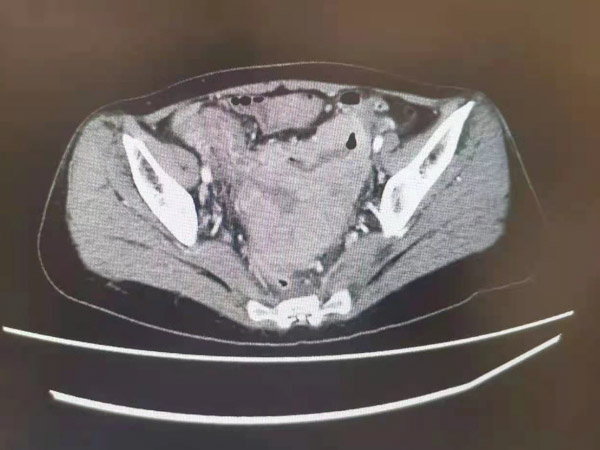

2020年9月,57岁的患者李阿姨因为腹胀、排便困难到我院就诊,经完善相关检查后,发现李阿姨盆腔内有一颗(7.5cmx11.1cmx8.6cm)肿瘤,相当于一个铅球大小。由于肿物太大,占满了盆腔,广泛侵犯子宫后下壁、左侧盆壁、右侧盆壁,暂时无法手术治疗,患者得知自己的病情,惴惴不安的心跌到了谷底。“阿姨,您放心,我们会尽100%的努力去解决您的问题!”我院胃肠外科负责人贺孝文不停为患者打气,这犹如一颗定心丸,让李阿姨恢复了战胜病魔的信心。

经过系统治疗,医患双方的坚持和不懈努力,转化治疗有效,盆腔肿物不断缩小,2021年7月,MDT团队通过对患者复查CT结果慎重、严格评估,肿物已由不可切除转化为可切除。7月20日,胃肠外科手术团队为李阿姨实施了腹腔镜下直肠根治性切除术,彻底将盆腔内的“定时炸弹”解除了。